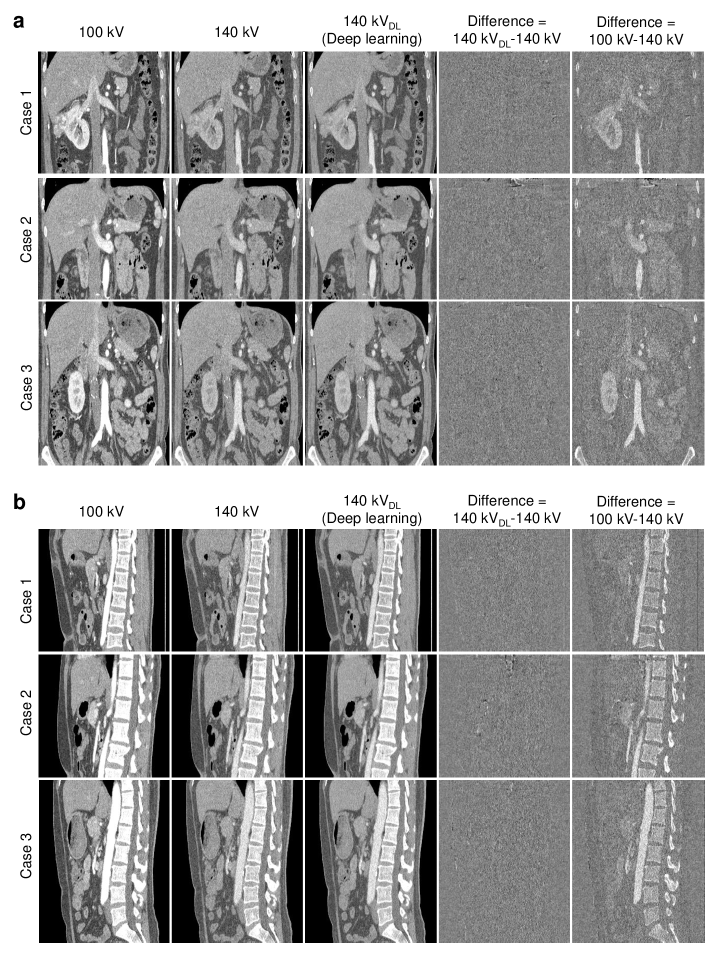

Figure 6: Raw DECT and DL-DECT images. a, The first and second columns display the raw 100 and 140 kV CT images for three testing patients who underwent contrast-enhanced DECT imaging. The third and sixth columns show the DL-predicted 140 kV images and their differences with respect to the corresponding raw 140 kV images. For comparison, the fourth and fifth columns show the difference images between the raw DECT images, and the difference images between the raw 100 kV and DL-predicted 140 kV images. b-e, Absolute HU differences between the raw and DL-predicted 140 kV images for ROIs in aorta, liver, spine and stomach, respectively. All CT images are displayed with a window width W = 500 HU and a center level C = 0 HU, while all difference images are displayed in a tighter window (C = 0 HU and W = 300 HU).

The denoised DECT images are then used for the training and testing of DL-DECT. Fig. 6 shows the raw DECT images (without denoising) and DL-DECT images for the three testing cases. Note that HU values of the iodine contrast in the 140 kV images are lower than that in the 100 kV images because the attenuation coefficient decreases with energy. In Fig. 6a, the first, second, and the third columns show the raw 100 kV, 140 kV, and the DL-predicted 140 kV images in transverse plane, respectively. The difference images between the DL-predicted and the raw 140 kV (ground truth) images are shown in the sixth column. For completeness, the difference images between the raw 100 kV and 140 kV images are shown in the fourth column along with the difference images between the raw 100 kV and the DL-predicted 140 kV images (the fifth column). It is seen that the DL-predicted 140 kV images are highly consistent with the ground truth images, with only some insignificant difference at the boundaries of anatomical structures, which may be due to the anatomical differences between the raw DECT images (the low- and high-energy data were acquired approximately 90superscript9090^{\circ} out of phase using a dual-source DECT scanner). It is intriguing that the DL-DECT imaging model is capable of accurately generating the image content of the raw 140 kV images, even in the regions where the differences between the raw low- and high-energy DECT images are large (Fig. 6a, the 4th column). Figs. 6b-e show the absolute HU differences between the predicted 140 kV and the ground truth images in the ROIs in the aorta, liver, spine and stomach, respectively. For the aorta and spine, the five ROIs are from the upper to lower abdomen, whereas, for the liver and stomach, the five ROIs spread the organs. It is found that the HU values of the DL-predicted images in all ROIs agree with the ground truth values better than 3.1 HU, indicating the potential of the DL-DECT imaging model for clinical applications.

Figure 7: Comparison between the raw DECT images and the DL-DECT images. a, Coronal plane; b, Sagittal plane. For both planes, the first and second columns show the raw 100 and 140 kV CT images of three testing patients, respectively. The third and fourth columns show DL-predicted 140 kV images and their differences with respect to the raw 140 kV images. All the CT images and the difference images are displayed with W=500 HU and C=0 HU.

Table 2 (in Appendix) shows the comparison of the HU values in all ROIs in the DL-predicted and the raw 140 kV images. Statistical analysis indicates there are no significant differences between the DL-predicted images and the raw CT images. The absolute HU differences between the DL-predicted and the ground truth 140 kV images are 1.3 HU, 1.6 HU, 1.8 HU, and 1.3 HU (corresponding maximum absolute HU differences are 3.0 HU, 2.9 HU, 3.1 HU, and 3.0 HU) for the ROIs in the aorta, liver, spine and stomach, respectively. Here the absolute HU difference for a given type of tissue is evaluated by averaging the values of all ROIs in the same organ of the 3 cases. The averaged absolute HU difference for each type of tissues is found to be less than 2 HU. The comparison between the predicted and raw 140 kV images in coronal plane and sagittal plane are shown in Fig. 7.